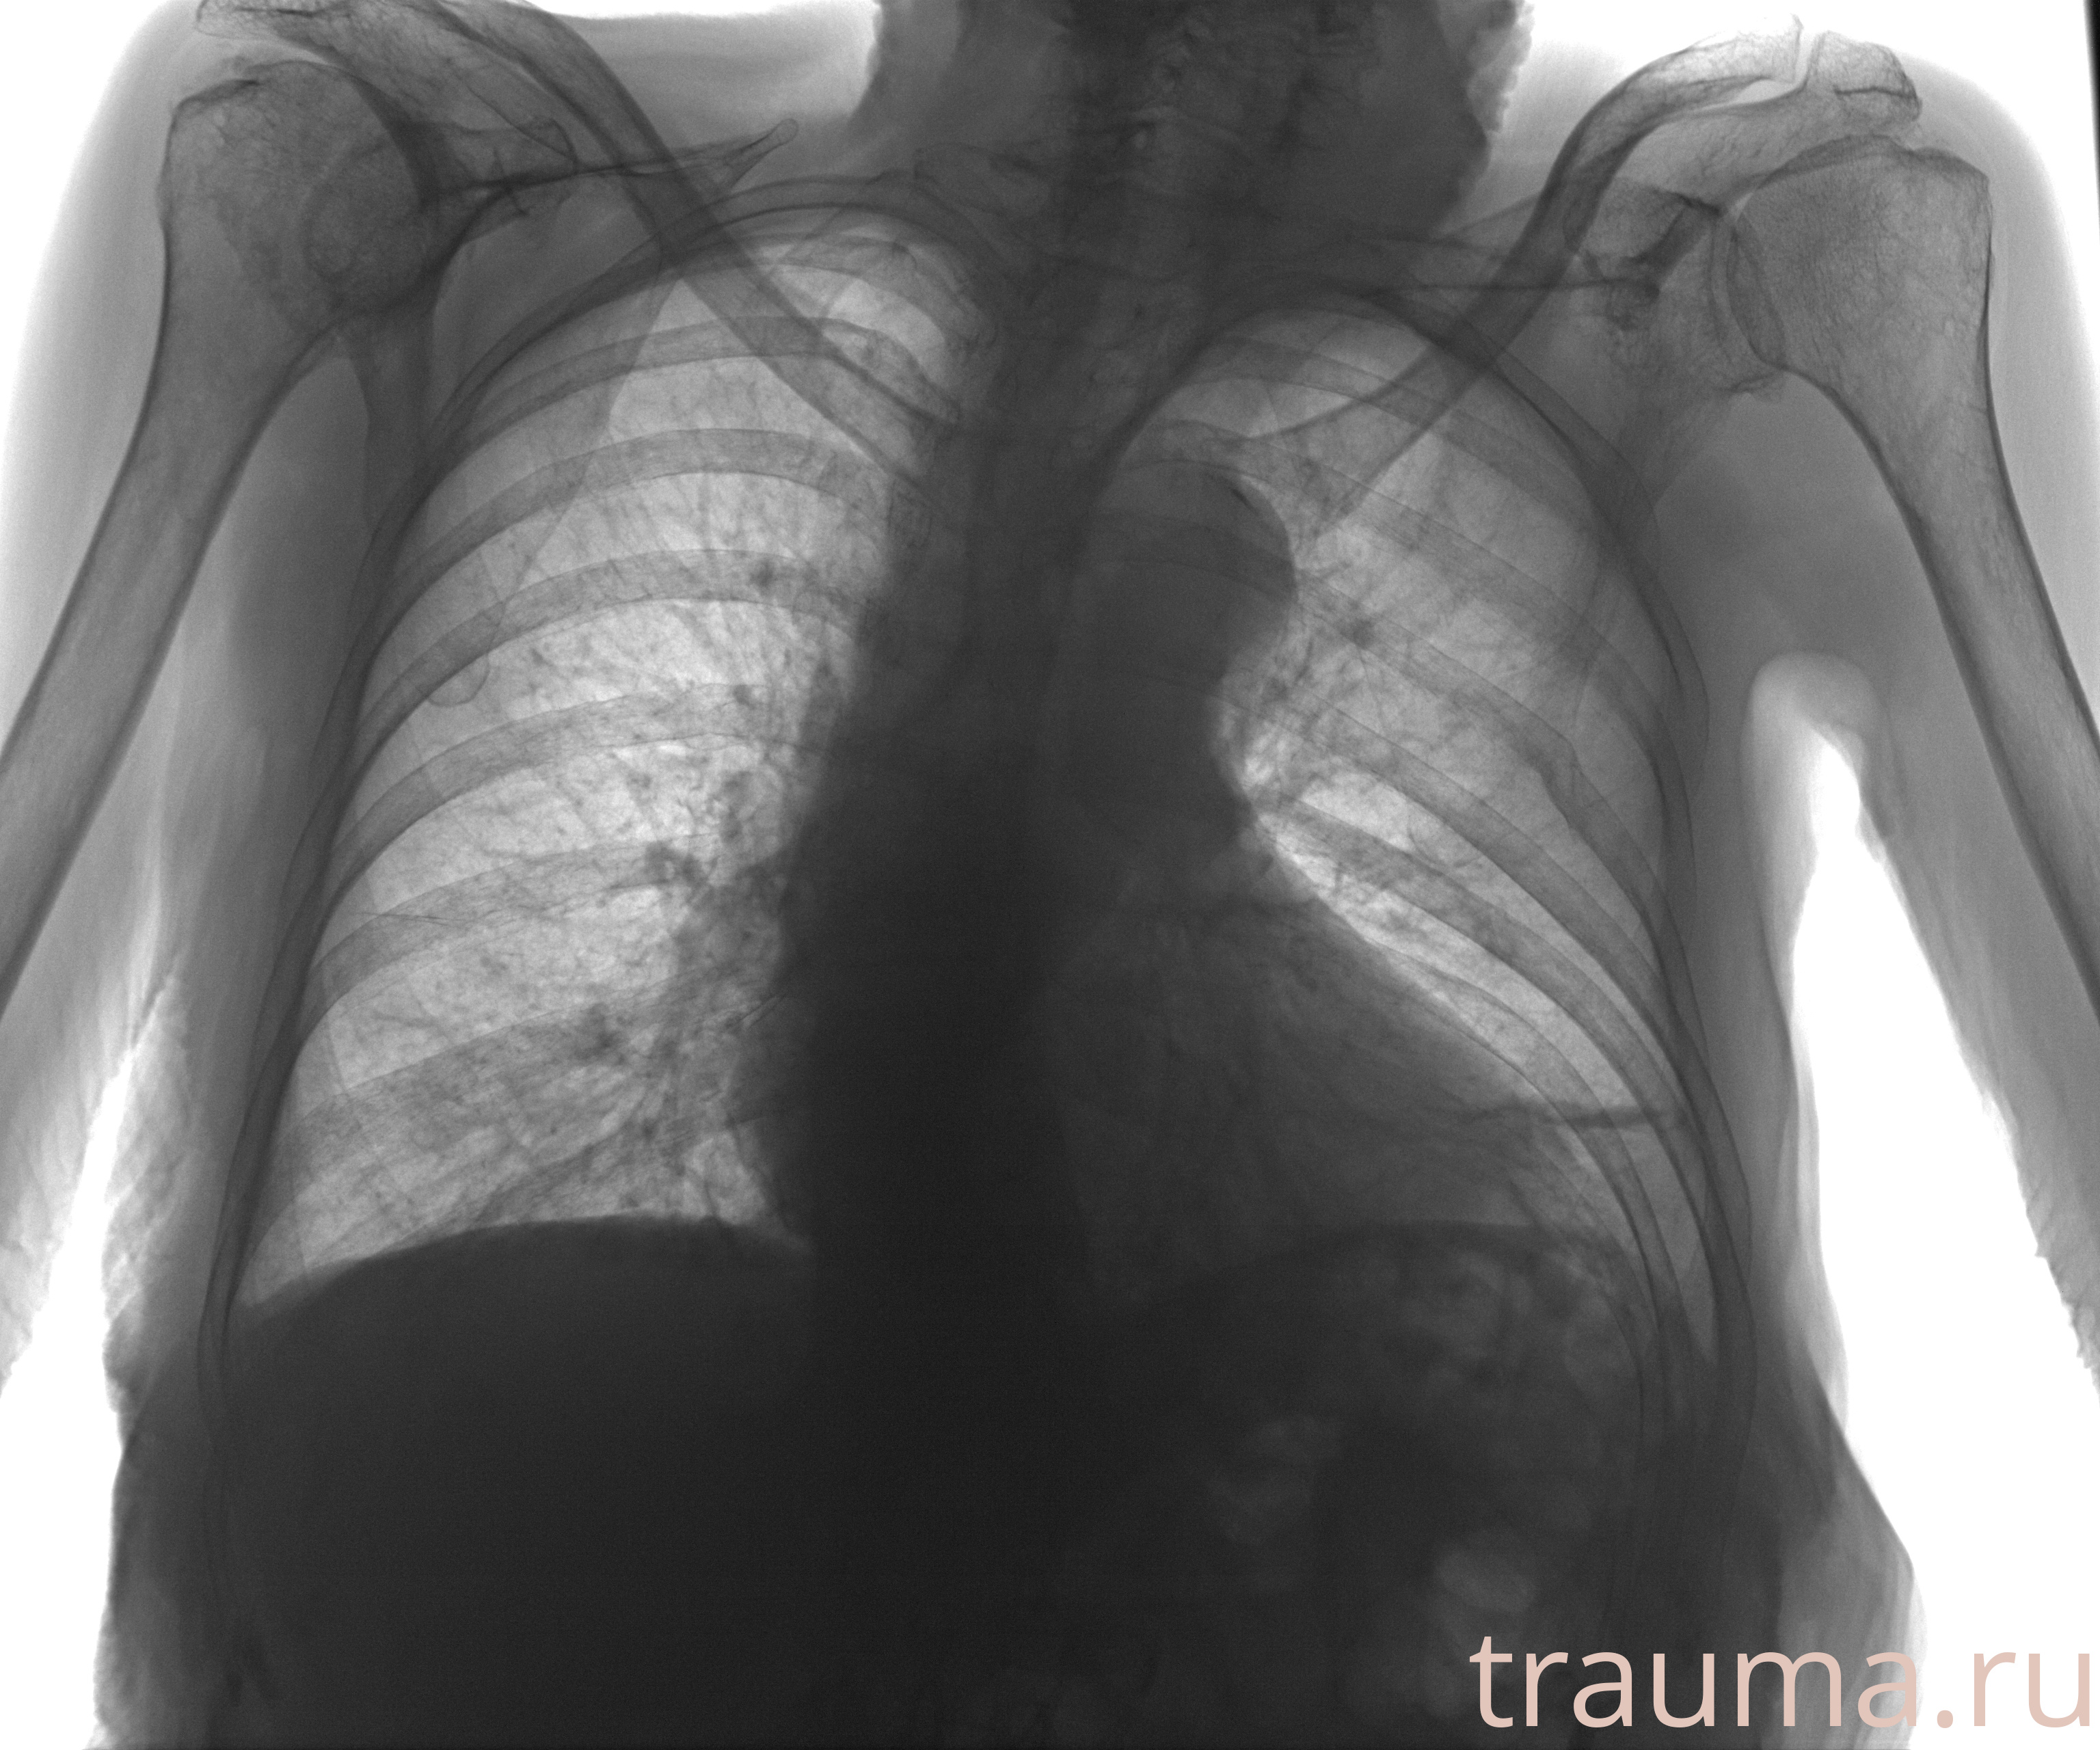

Рентген на дому: по вашему адресу приезжает врач-рентгенолог, травматолог-ортопед с мобильным рентгеновским аппаратом, проводит диагностику травмы или заболевания, делает необходимые рентгенограммы, дает рекомендации по дальнейшему лечению. Получить качественные снимки в домашних условиях возможно благодаря уникальной методике, разработанной МосРентген Центром для института  Склифосовского

при переломе шейки бедра и пневмонии от компании МосРентген Центр - партнера Института имени Склифосовского